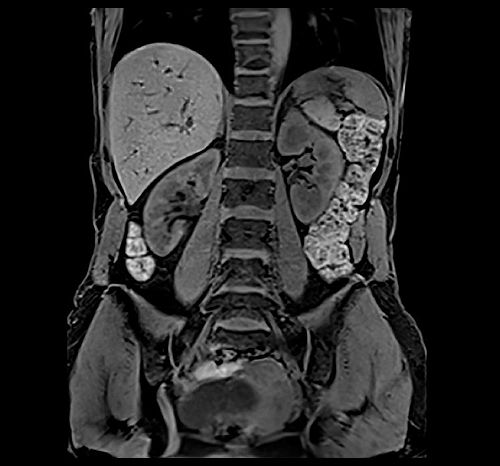

Ο Magnetom Lumina διαθέτει πολυκάναλα πηνία τελευταίας τεχνολογίας για υψηλής διαγνωστικής αξίας απεικόνιση της ανατομίας και της λειτουργίας όλων των περιοχών του ανθρωπινου σώματος. Διαθέτει δυνατότητα πραγματοποίησης όλου του φάσματος των εξετάσεων Μαγνητικής Τομογραφίας, όπως νευρολογικών, ογκολογικών, μυοσκελετικών, καρδιολογικών εξετάσεων, καθώς και ειδικές εξελιγμένες τεχνικές απεικόνισης. Κάποιες από αυτές της ειδικές εξετάσεις είναι ολοσωματική μαγνητική τομογραφία, τεχνική μείωσης παρασίτων από συμβατά με μαγνητικό τομογράφο μεταλλικά εμφυτεύματα, παραμετρικοί χάρτες καρδιάς για διάγνωση αρχόμενης ισχαιμίας, στεφανιογραφία χωρίς έγχυση σκιαγραφικού, μελέτη αιμάτωσης εγκέφαλου, πολυπαραμετρική προστάτη, μαγνητική μαστογραφία, μέτρηση αιμάτωσης εγκέφαλου, μέτρηση σιδήρου και λίπους του ήπατος, δυναμική αγγειογραφία.

Απεικόνιση 1